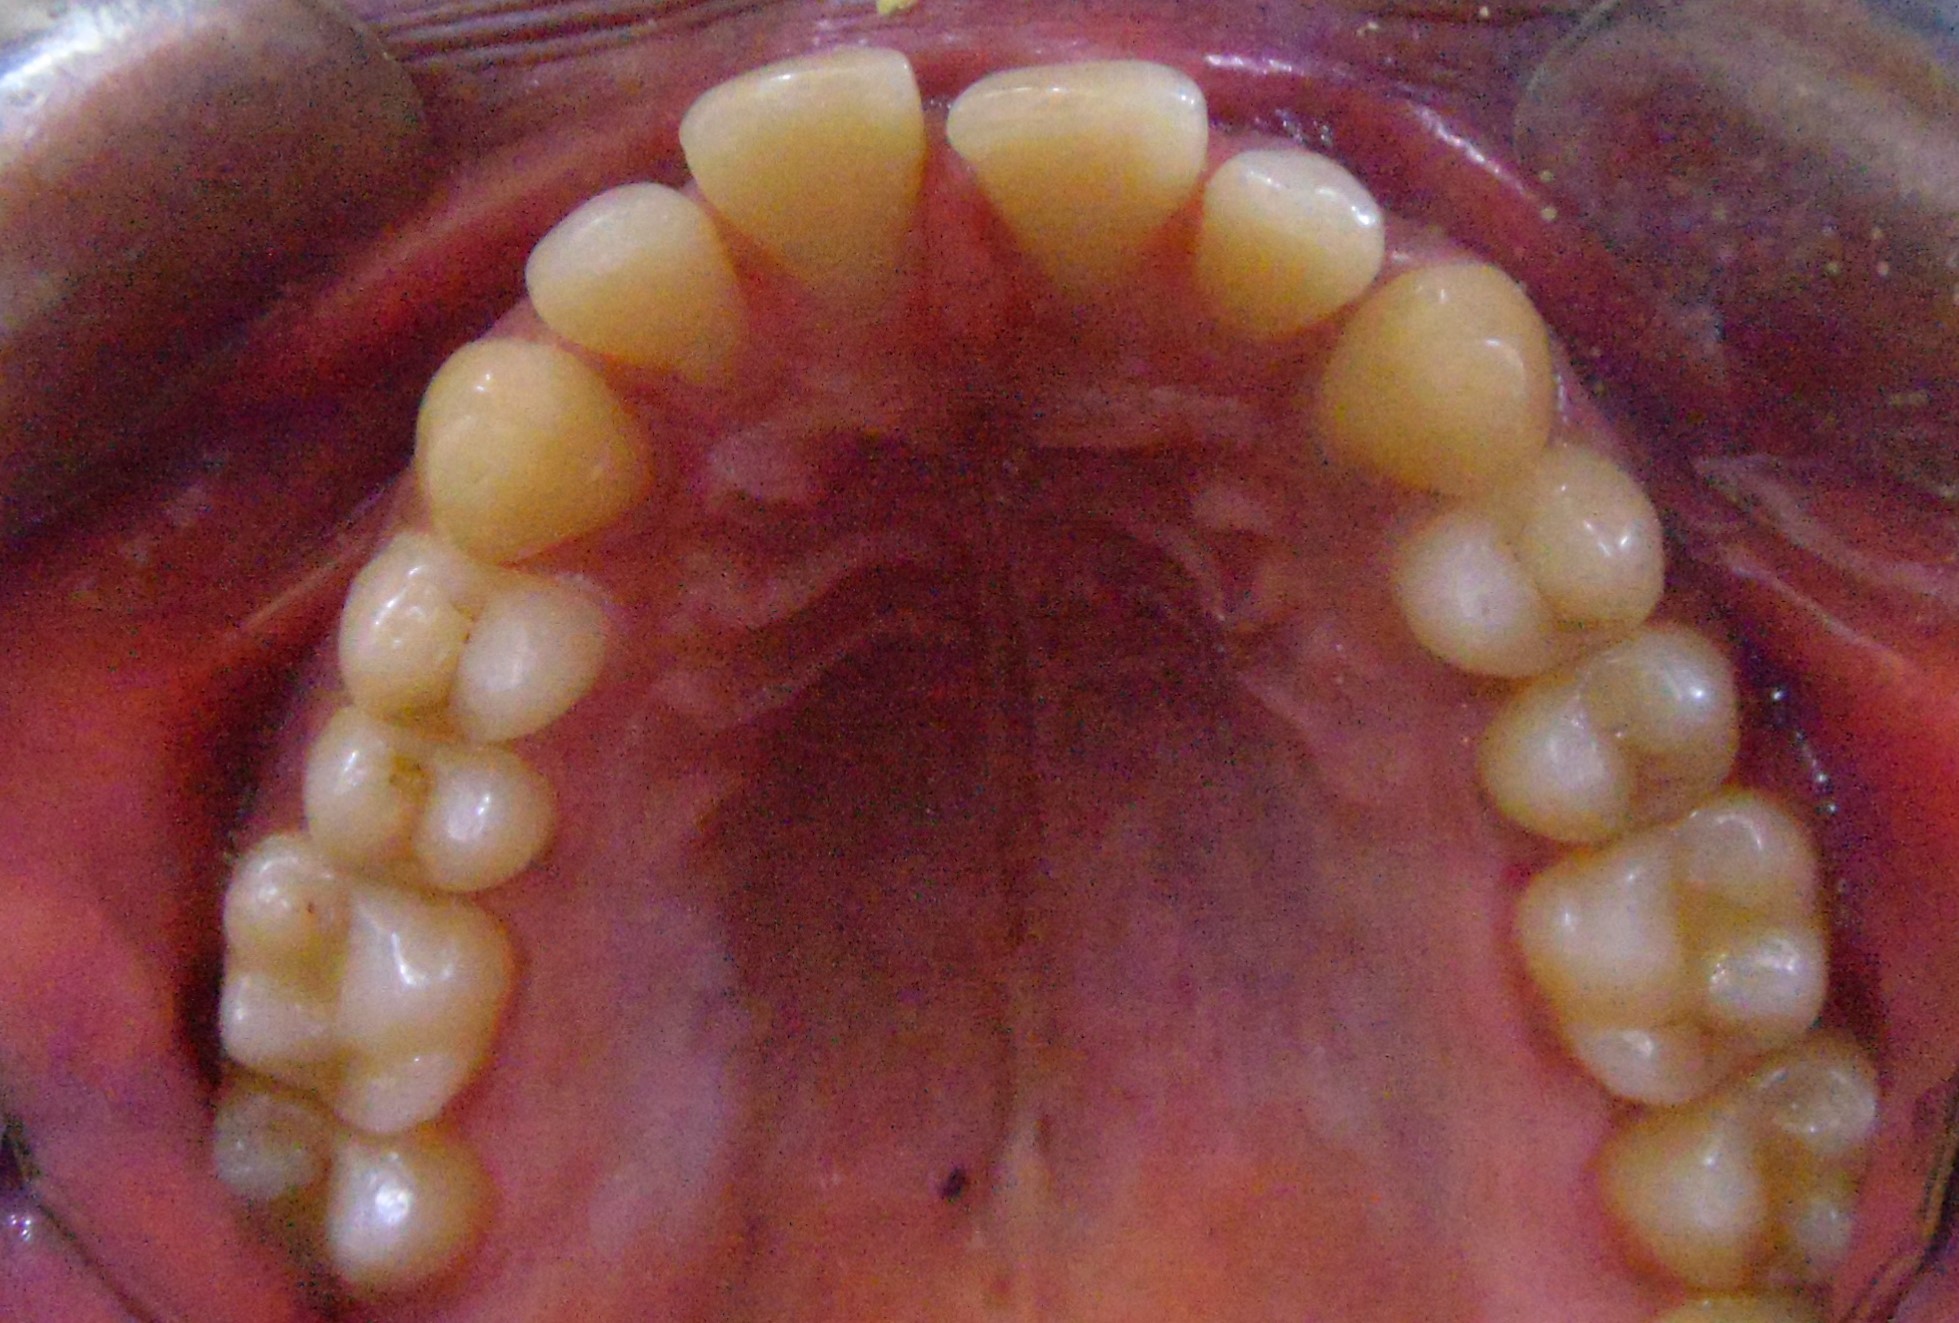

Before

After

Image 1